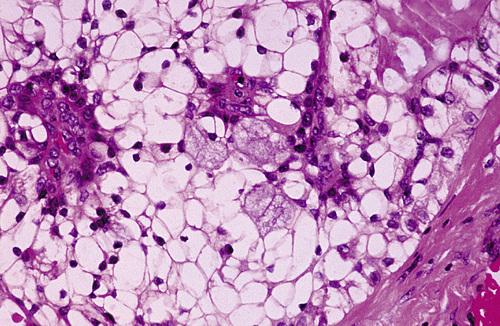

Histopathologic Features

- hypertrophy of acinar cells

- nuclei displaced to cell base

- cytoplasm engorged with zymogen granules

- acinar atrophy and fatty infiltration

- no inflammation

sialadenosis

Enlargement of the parotid and submandibular glands secondary to alcoholism. Sialography demonstrates a “leafless tree” pattern.